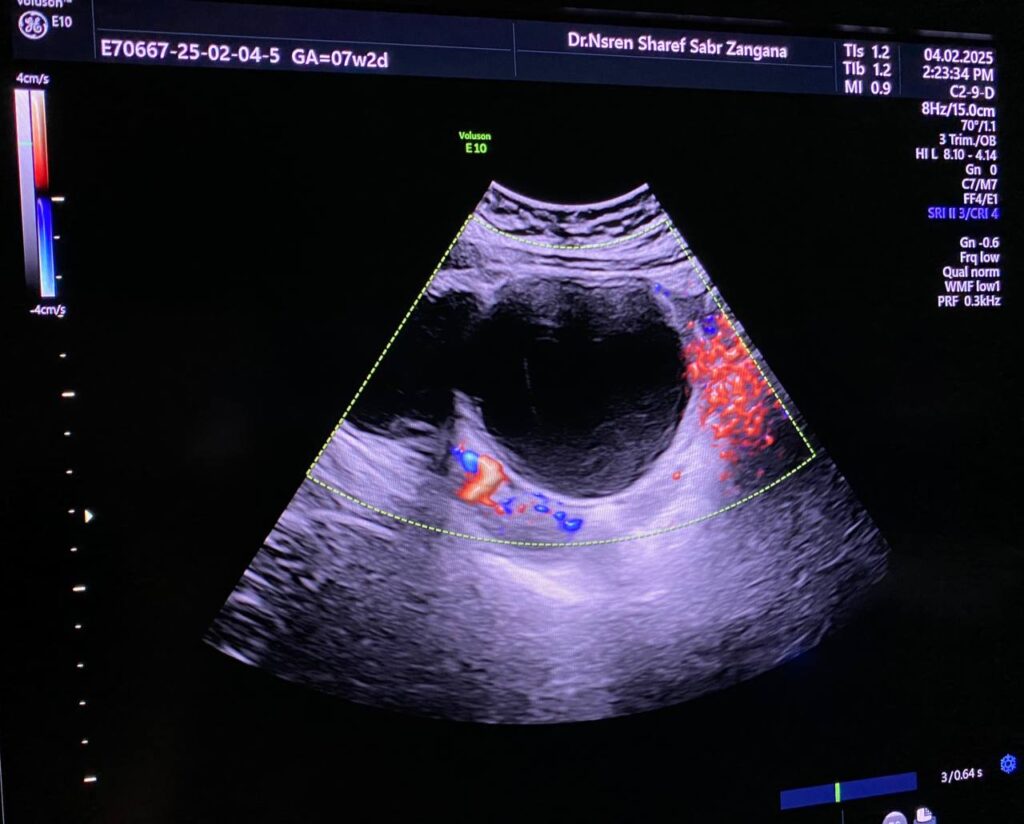

Left ovarian avascular cystic mass 71x68mm , with adjacent left adnexal mass 30x30mm , picture mostly of twisted ovarian pedicle , associated with free fluid >40ml , please for further study to excluded other pathology

Lt ovary is enlarged and edematous, contains 7cm thin wall unilocular cyst “ORADS 1”, there is twisting of its vascular pedicle, picture of ovarian torsion.